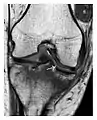

Figure 8: Proximal diaphyseal fatigue fracture of the tibia in a 20-year-old man with a history of regular jogging. (a) Lateral radiograph shows no obvious fracture lines but a subtle localized medial tibial cortex periosteal reaction (arrows). (b) Sagittal reformatted CT image acquired 1-month after the radiograph shows a linear hypoattenuation in the tibial cortex (arrowhead), as well as obvious periosteal thickening (arrows). (c) Sagittal T2-weighted fat-saturated image acquired the same day shows an area of hyperintensity spreading over the proximal tibia (arrows), which is consistent with the presence of proximal tibial fracture.[1]